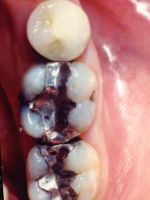

Before

After